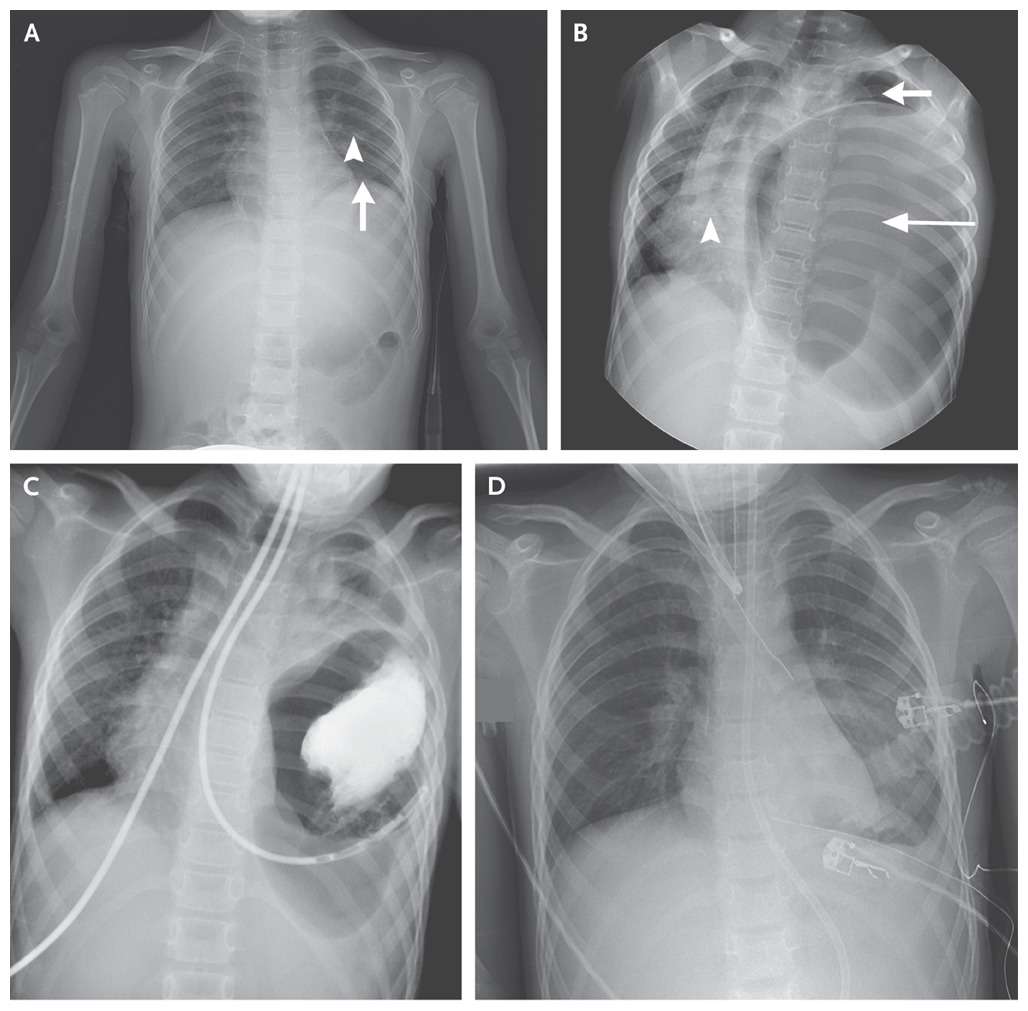

A postoperative anteroposterior plain radiograph (Panel A) showed a raised left hemidiaphragm (arrow) and a left chest tube (arrowhead) that had been placed earlier to drain a left hemothorax. The boy was discharged from the hospital after recovering from his injuries.

At the time of the current presentation, physical examination revealed no breath sounds over the left hemithorax. Anteroposterior plain radiography of the chest (Panel B) showed a large, gas-filled structure in the left hemithorax (long arrow), near-complete collapse of the left lung (short arrow), and a marked rightward shift of the mediastinum (arrowhead).

The left hemidiaphragm could not be clearly seen. After the administration of contrast material through a nasogastric tube, repeat chest radiography was performed and confirmed that the stomach lay within the left hemithorax (Panel C).